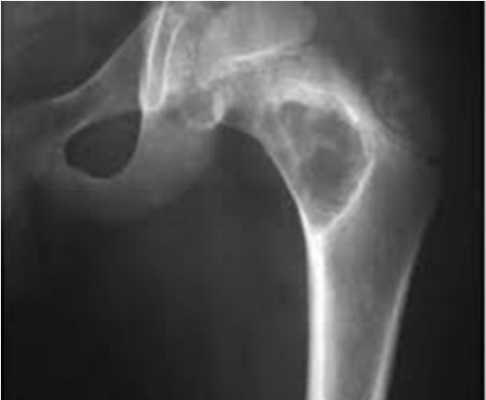

Снимок 3. Здесь представлен снимок пациентки, которой диагноз «коксартроз» поставили вовремя, еще на первой стадии болезни. Но, несмотря на своевременно поставленный серьезный диагноз, сама пациентка очень безалаберно отнеслась к своему здоровью и 5 лет игнорировала назначенное врачами правильное лечение. Вот что представлял ее сустав через 5 лет:

- суставной хрящ разрушен почти полностью (нет расстояния между костями, головка бедренной кости почти полностью «вклинилась» в вертлужную впадину);

- головка бедренной кости сильно деформирована, цвет верхней части головки на рентгене выглядит светлее (признак микроперелома костных балок из-за повышенного давления на верхнюю часть головки).

Коксартроз 3-й стадии. Фотография из архива доктора Евдокименко

Все эти рентгенологические признаки соответствуют коксартрозу третьей стадии. Третья стадия коксартроза была также подтверждена во время осмотра пациентки. К сожалению, из-за того, что пациентка халатно отнеслась к своему здоровью и не стала лечиться вовремя, ей пришлось идти на операцию по замене тазобедренного сустава.